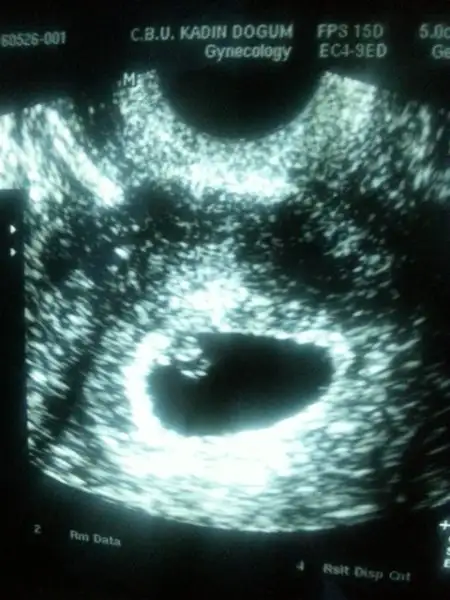

Eki Görüntüle 1847341 bu bebegimin 9 haftalik usg resimi... :) burda ne gibi?